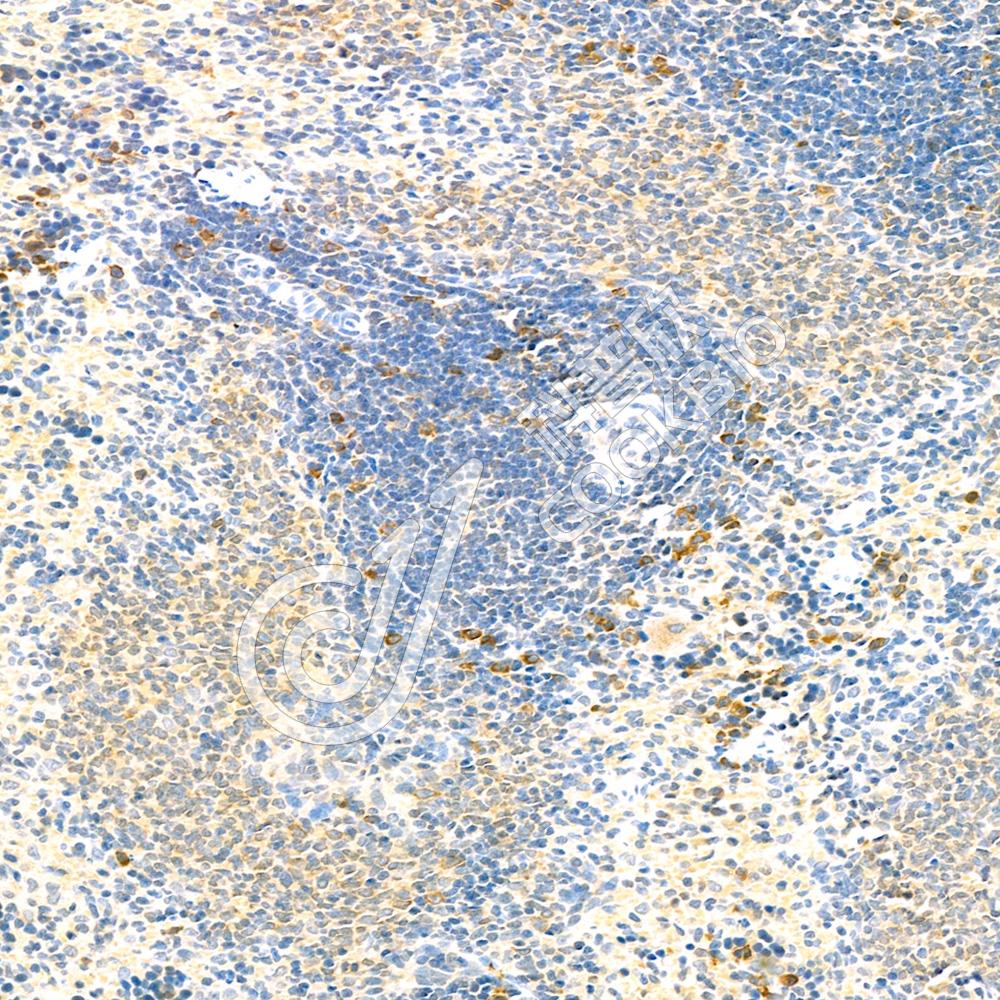

IHC检测Proteasome 20S beta 6蛋白(货号 K1335853).

样品: 人结肠癌, 4%多聚甲醛 (货号KSG1101) 固定12-24小时.

抗原修复: 柠檬酸抗原修复液(干粉, pH 6.0) (KSG1201), 98℃, 20分钟.

—抗: 1: 900稀释, 4℃ 孵育过夜.

二抗: S-vision免疫组化多聚二抗(山羊抗兔),即用型 (货号KB3906), 室温孵育20分钟.